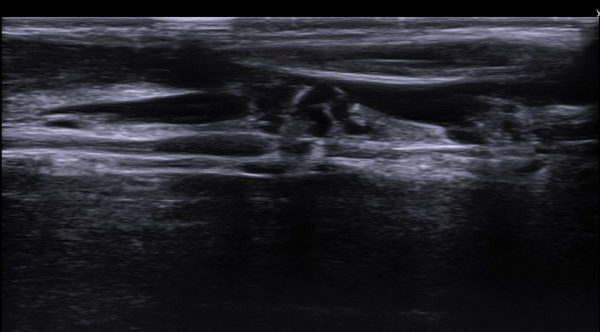

ÃÊÀ½ÆÄ ¼Ò°ß  : »ó¹Ú ³»Ãø ±ÙÀ°ÇǺνŰæ Ⱦ´Ü¸é°Ë»ç ¿¡¼­ ±ÙÀ°ÇǺνŰæÀÇ Àú¿¡ÄÚ ºÎÁ¾ÀÌ °üÂûµÈ´Ù(»çÁø 1).

Å½ÃËÀÚ¸¦ Á¶±Ý ¸»´ÜÀ¸·Î À̵¿ÇÏ´Ï ±ÙÀ°ÇǺνŰæÀÇ À§ÃàÀÌ °üÂûµÇ°í(»çÁø 2) ŽÃËÀÚ¸¦ Á¶±Ý ´õ